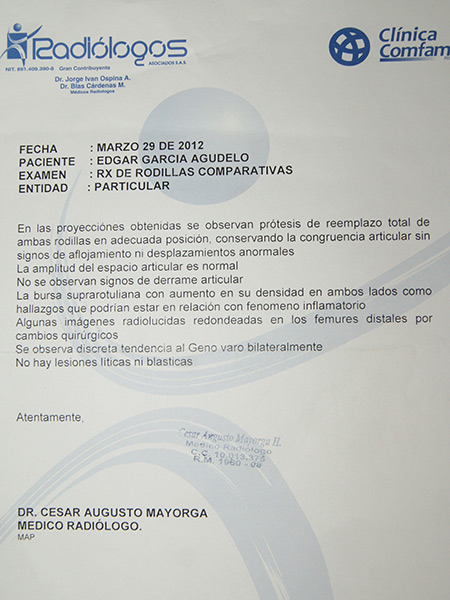

Las rodillas mecánicas de El Dandy

El alta médica